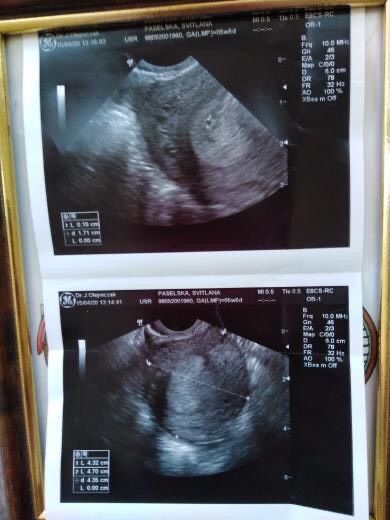

Врач очень долго не мог ничего найти ,очень забеспокоилась.Спустя время нашёл вот это.Предпологаемый срок 5 акушерских недель(ембриональный 2,5-3недели)Но нечего толком не объяснил и сказал что матка не расширенная,а должна бы.Спросил а точно ли я беременная и странно что тест показал две полоски.Сказал придти через две недели.Волнуюсь теперь.

В этот раз у меня овуляция поздняя была, в 5 н 4 д по месячным ни намека на беременность на узи не было, хотя тесты уже показывали. В 6 н 6 д уже и сердце билось на узи. Подождите недельку-две, тогда точно все увидите.

У меня была поздняя овуляция, по этому увидели только в 6 недель

Акушерский срок считается от первого дня последних месячных, а эмбриональный недели на две позже. Я тоже думаю, что рано ещё для узи.